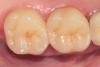

dr.moskvichev Опубликовано 17 августа, 2013 Поделиться Опубликовано 17 августа, 2013 После удаления композита и кариеса выбор пал на керамические вкладки. Временные реставрации изготовил из Protemp 4 по ключу из силикона, обработал дентин-герметизующим ликвидом, дебондинг,одномоментный двухслойный оттиск Express, временная цементировка на Temp NE. Техническая работа заняла неделю Времяшки выдержали, зубы не болели, незначительная гиперестезия к концу недели. Фиксировал на вариолинк 2. На следующий день после фиксации отмечалась слабовыраженная гиперестезия, которая исчезла на второй день. Основной вопрос: Будут ли такие конструкции состоятельные в отношении прочности(особенно при боковой нагрузке) в отдаленные результаты? Вопрос назрел в связи с большим межокклюзионным растоянием между буграми препарированных зубов и антагонистов (коронки м.к). Хватит ли силы адгезии для удержания таких крупных вкладок? Спасибо за внимание. 11 Ссылка на комментарий

dr.moskvichev Опубликовано 17 августа, 2013 Автор Поделиться Опубликовано 17 августа, 2013 (изменено) Согласен. Редукцию небных всё же сделал бы,вероятно. Так,как в кейсе, не точил бы,скорее - надстроил бы кором - и запилил под полные коронки,чем так. P.s. Но кейс аккуратный.Редукция небных практически до десневого уровня, что обусловлено большей окклюзионной нагрузкой на них. А вот с щечной стороны пожалел ткани- в ущерб эстетике, но с минимальной инвазией. По цвету получилось приемлимо, после полировки граница и переход видны минимально. Изменено 17 августа, 2013 пользователем dr.moskvichev Ссылка на комментарий

dr.moskvichev Опубликовано 17 августа, 2013 Автор Поделиться Опубликовано 17 августа, 2013 А мне нравится, работа аккуратная. Чем полировали?Софлексы, тонкие штрипсы, конические и чашевидные полиры, паста клинпро. Спасибо. Ссылка на комментарий